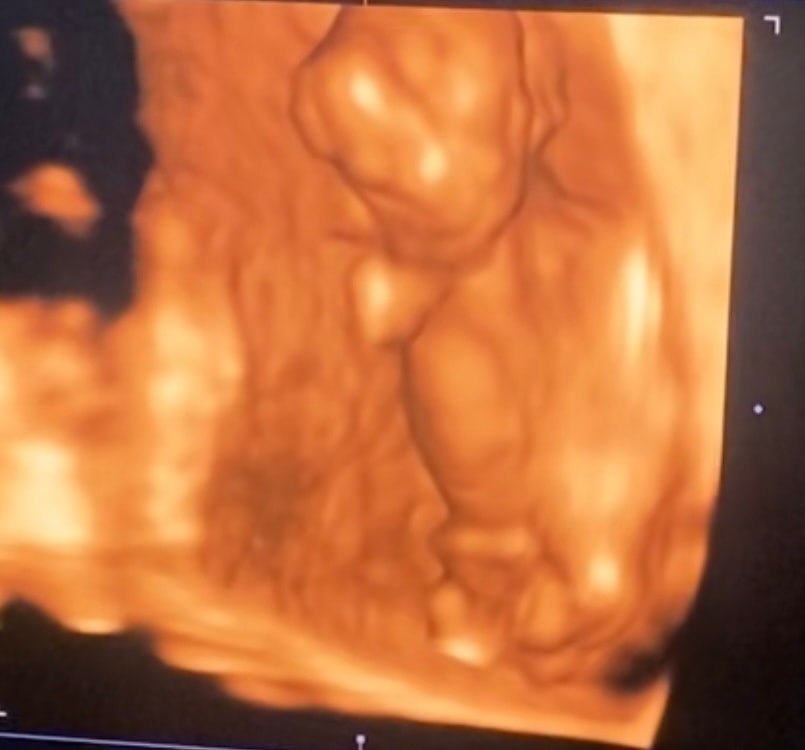

Изображение

31.10.2025

Жасмин К, мне кажется мальчик,хотя если честно возможно и половые губы формируются. На 16 неделе будет уже ясно точно,подождите немного. Ну или сделайте анализ на определение Пола ребенка

Жасмин К, это девочка

Жасмин К, бугорка полового особо не видно, и пуповинка закрывает. Вам если надо быстро точно и срочно, вы сдайте кровь на определение пола ребёнка, он вроде 3-5 дней готовится